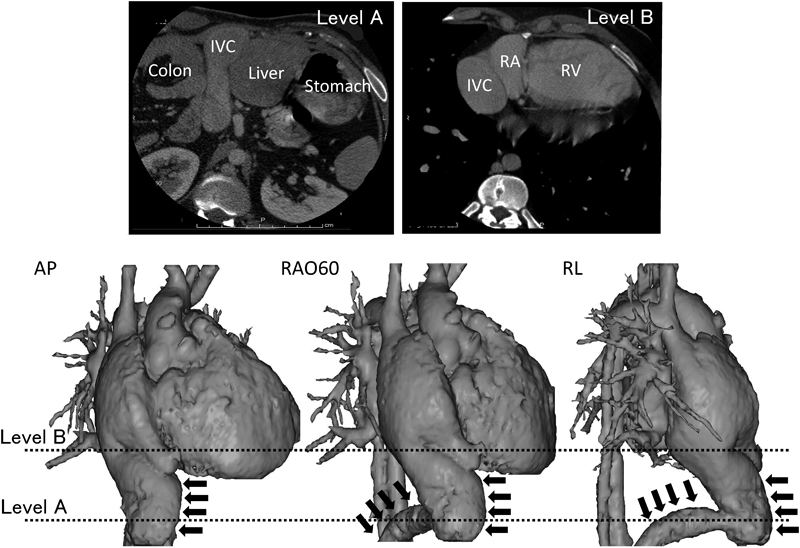

Fig. 1 Enhanced cardiac computed tomography (CT) (top) and three-dimensional reconstruction of CT angiography images (bottom)

At the subdiaphragmatic portion (Level A), the inferior vena cava (arrows) turned anteriorly and ran superiorly. It was connected to the anterolateral portion of the right atrium (Level B). IVC, inferior vena cava; RA, right atrium; RV, right ventricle; AP, anterior-posterior view; RAO60, 60-degree anterior oblique view; RL, right lateral view.

At the beginning of the procedure, we attempted catheter entry via the femoral veins. At the subdiaphragmatic level, however, vascular obstruction was suspected. Venography revealed marked angulation of the inferior vena cava (IVC) (Fig. 1). Because of significant limitations in the number of insertable catheters and inoperability by the femoral venous approach, we switched to right internal jugular venous access. Using a three dimensional electroanatomical mapping system, the patient’s induced clinical arrhythmia was diagnosed as common atrial flutter. Linear ablation was performed at the cavo-tricuspid isthmus. However, it was difficult to confirm blocking lines because of the limited number of diagnostic electrode catheters, and his arrhythmia was not inducible at the end of the session. He remained recurrence-free during 3 years of follow-up.